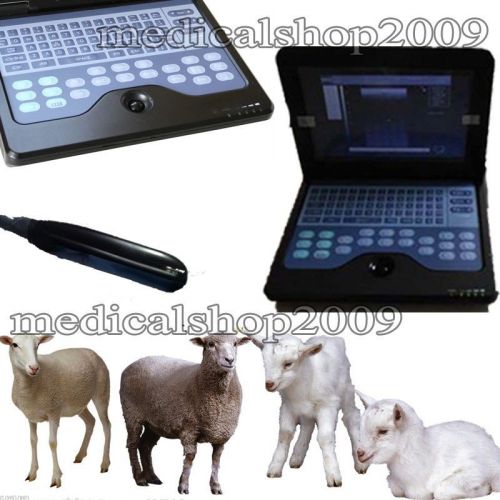

Veterinary Laptop B-Ultrasound Diagnostic System scanner 3.5mhz covex probe P2

3D Digital portable animal Veterinary Ultrasound Scanner machine w rectal probe

Hot!! CMS600P2 VET veterinary Laptop Ultrasound Scanner System 6.5M Rectal Probe